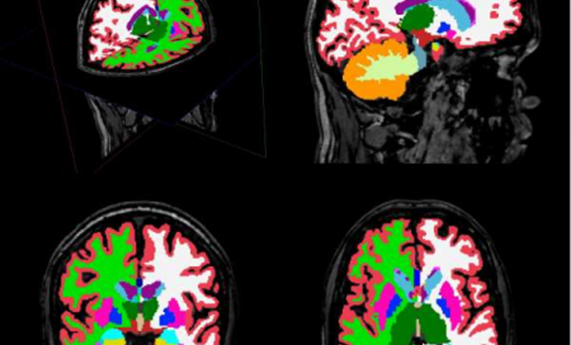

Describen alteraciones en estructuras cerebrales en pacientes con esquizofrenia descubiertas mediante un innovador análisis de imagen cerebral